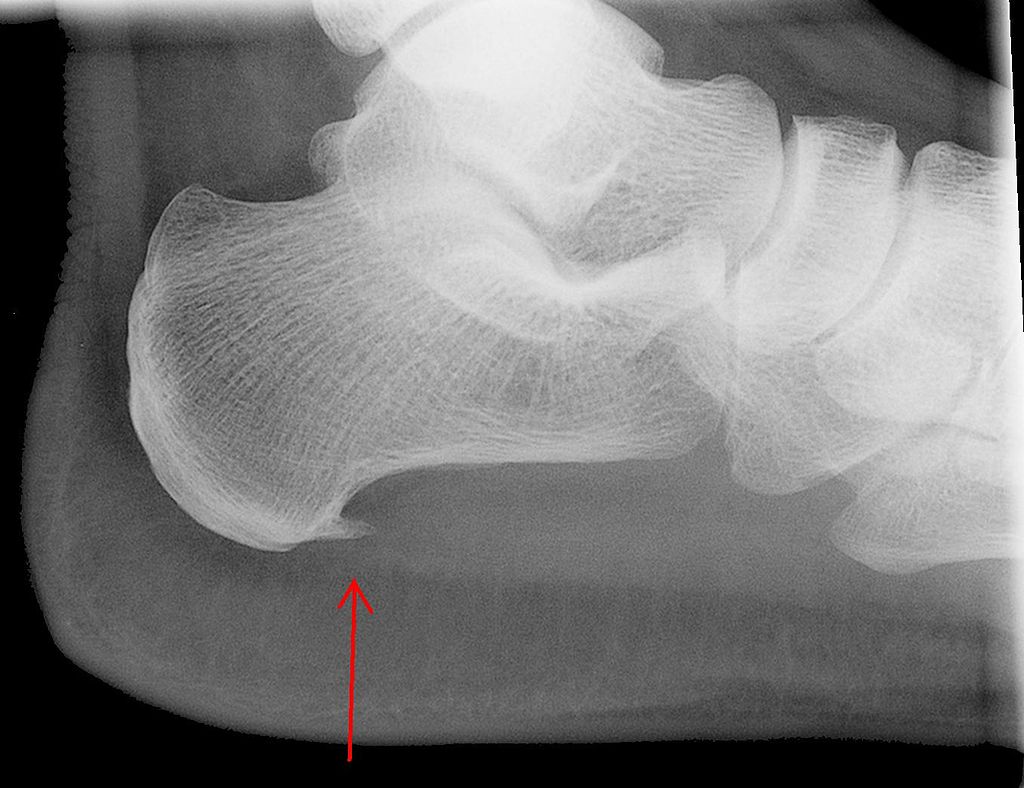

Для диагностики остеофитов применяется рентгенологическое исследование костей. Более информативным методом является МРТ, который позволяет выяснить причины появления пяточной шпоры и получить данные о состоянии окружающих тканей. На поздних стадиях крупные наросты могут быть видны при визуальном осмотре и прощупывании. Тем не менее, для оценки степени заболевания и структуры остеофитов потребуется рентгенологическое исследование.